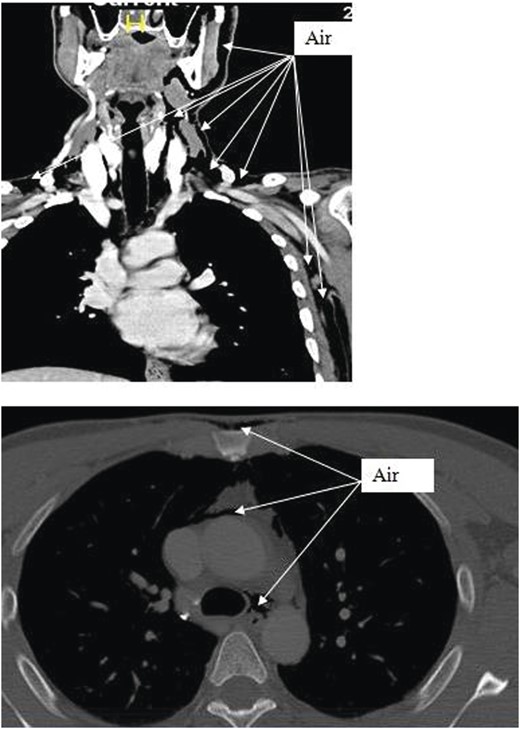

Chest X-ray and head, neck and chest computed tomography (CT) confirmed the diagnosis and extension of PM (Figs 1–3). CT revealed fracture of the floor of left orbit with soft tissue, fat herniation into left maxillary sinus roof, left orbital emphysema with no muscular entrapment. Gas was observed in periorbital tissues, left temporal scalp, infratemporal fossa, left parapharyngeal space and left cheek. Moreover, tissue planes in the neck revealed the presence of air particularly around the carotid vessels, in the posterior triangle and superior mediastinum (PM) around the thymus, trachea (middle), left side of the aorta and anterior to the sternum. However, on auscultation, lungs were clear with and the laryngeal passages and trachea looked normal.

CT scan shows the extension of air from the face, neck and chest.